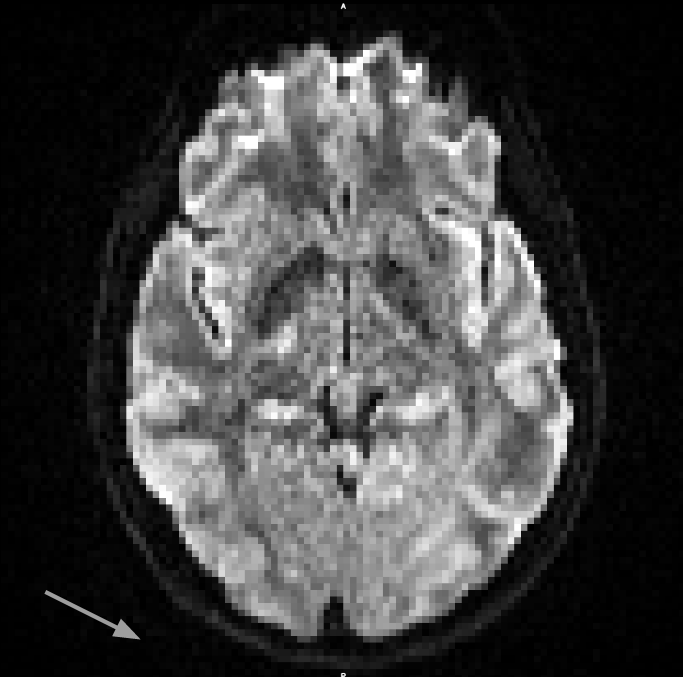

From these datasets, we use the five non-diffusion weighted () MRI scans each, as well as 30 diffusion weighted images (, diffusion gradient duration , spacing ). Each image consists of voxels with a resolution of . The data, and the effects of subject motion, are illustrated in Figure 6.

It can be seen in Figure 6 that subject motion during different phases of the acquisition leads to different types of artifacts. Results in Table 1 include the motion correction described in Section 3.3, which compensates spatial misalignments of different scans. However, motion can also lead to signal dropouts or to distortions within scans, which our current codec does not explicitly account for. This explains why q-space inpainting is less effective on the second as compared to the first scan. However, even on this challenging dataset that exhibits unusually strong artifacts, q-space inpainting still provides a benefit compared to all other alternatives.